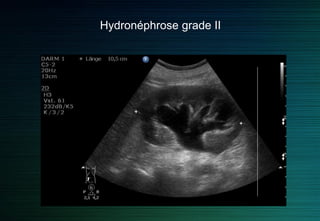

On différencie quatre grades d’hydronéphrose sur des critères échographiques

Grade 1 : dilatation du bassinet sans dilatation calicielle et épaisseur parenchymateuse normale.

Grade 2 : dilatation du bassinet et des calices avec amincissement du parenchyme.

Grade 3 : dilatation kystique du bassinet avec fin anneau du parenchyme.

Grade 4 : plus de parenchyme visible.

Hydronéphrose grade II